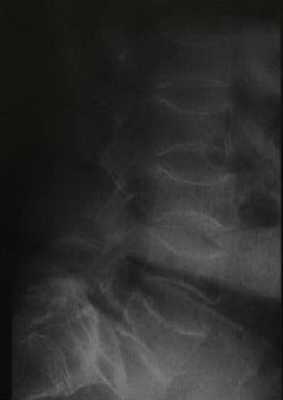

Взрослая форма несовершенного остеогенеза у мужчины 68 лет. На рентгенограмме поясничного отдела позвоночника определяются характерные «рыбьи» позвонки из-за наличия остеопороза.